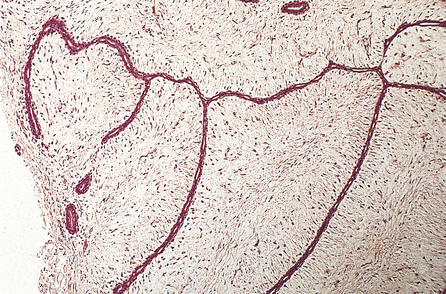

Histologically, they are composed of well-formed tubular structures, the cells of which show little pleomorphism or mitotic activity. The stroma is dense, often with elastosis (Fig. 18.25).

image

Fig. 18.25 Tubular carcinoma. Tubular profiles lie in a fibrous stroma.

Patients with tubular carcinomas do extremely well—better than those with well-differentiated invasive duct carcinomas.